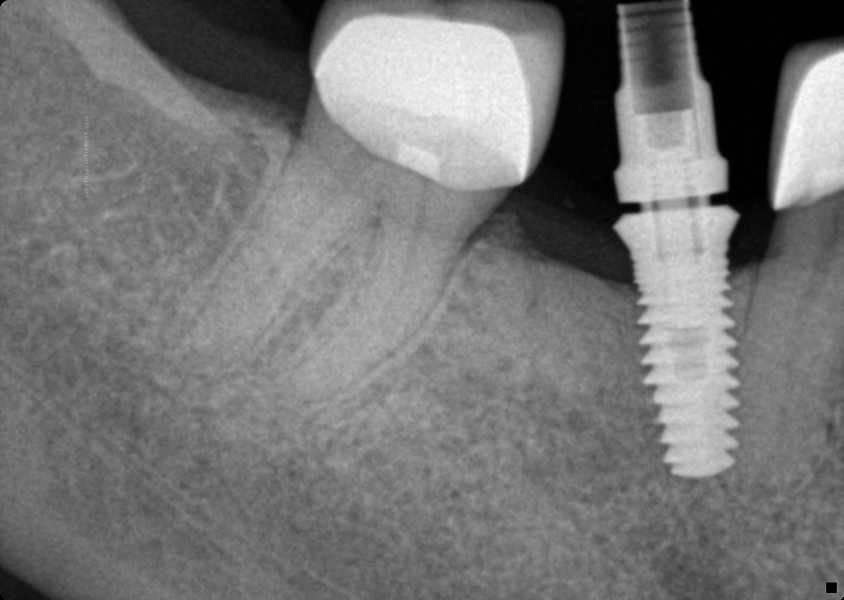

Body Shape

Tapered body

Thread Design

Threaded

Additional Features

CollarCurved apexFlared flangeReverse buttress